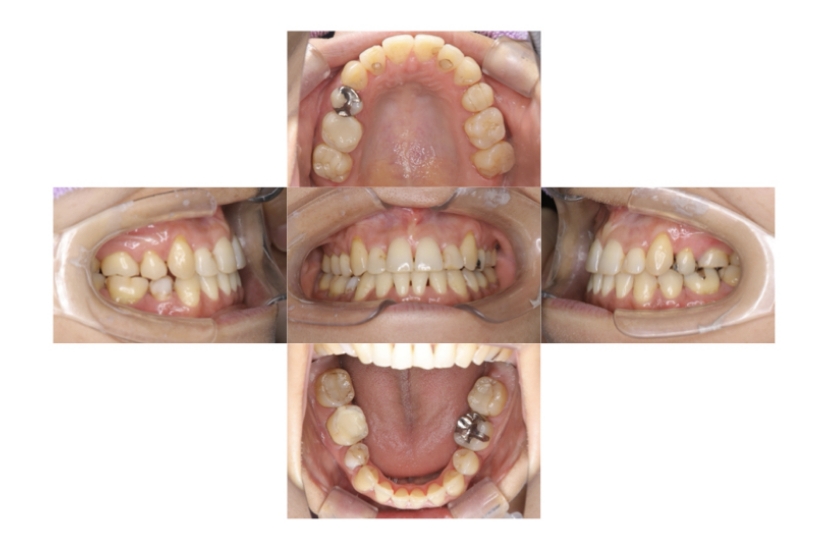

BEFORE

AFTER

上下顎叢生(上下の前歯のガタガタ)のケースです。

装置はラビアル(上下表側)で、上下顎の小臼歯を4本抜歯を行っています。抜歯したスペースを使って、上下の前歯の後方移動と叢生(ガタガタ)の改善を行っています。

主訴 八重歯を治したい。

年齢・性別 25歳 女性

お住まいの地域 神奈川県川崎市

治療方針 抜歯スペースを利用して上前歯の叢生(ガタガタ)の改善

抜歯部位 上下顎左右第一小臼歯

使用装置 ラビアル(上下表側)、顎間ゴム

治療期間 1年11か月

治療回数 16回

リテーナー クリアリテーナー